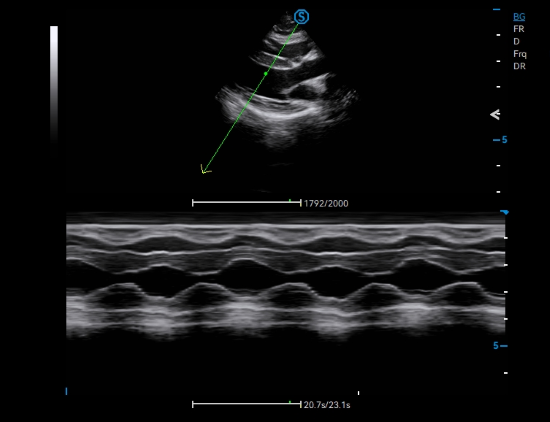

The robust computing capability of V9 Lite enables Broad Beam Transmission to calculates echo information through wide-band imaging processing, significantly enhancing the energy utilization rate and penetration level. Image quality is optimized by Tailored Filter and Intelligent Refactoring through noise filtering and effective extraction of echo information.

Adaptive TDI facilitates the evaluation of myocardial motion throughout the cardiac cycle, which is particularly crucial for elder dog examination.

AMM empowers assessment of cardiac wall motion with multiple sampling lines, thereby facilitating efficient diagnosis of dilated cardiomyopathy for large-sized canines